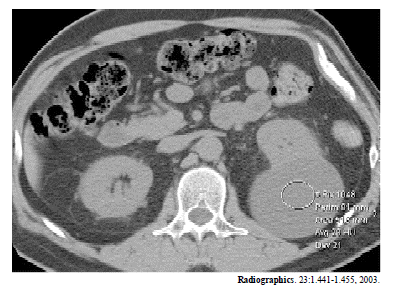

A figura acima mostra um corte de tomografia computadorizada de um homem com 47 anos de idade. Considerando essa imagem e as patologias a ela associadas, julgue os seguintes itens.

Quando a tomografia indica suspeição em um nódulo renal, a biópsia percutânea é recomendada.

Cistos renais são normalmente assintomáticos.